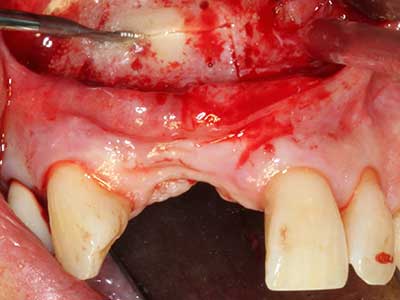

Piezo surgery has additional advantages when harvesting bone blocks. In addition to the high precision with osteotomy described above, the use of the thin saw tips specifically minimizes loss of material. Greater loss of material during harvesting can be expected with the thicker instrument tips, particularly when using Lindemann drills (Lakshmiganthan, Gokulanathan et al. 2012). The basal separation, which is necessary particularly for retromolar block transplants, is simplified by specially designed rectangular saws, with the result that piezo surgery is viewed as a precise, simple and safe procedure for harvesting retromolar bone blocks (Happe 2007) (Fig. 1-12).